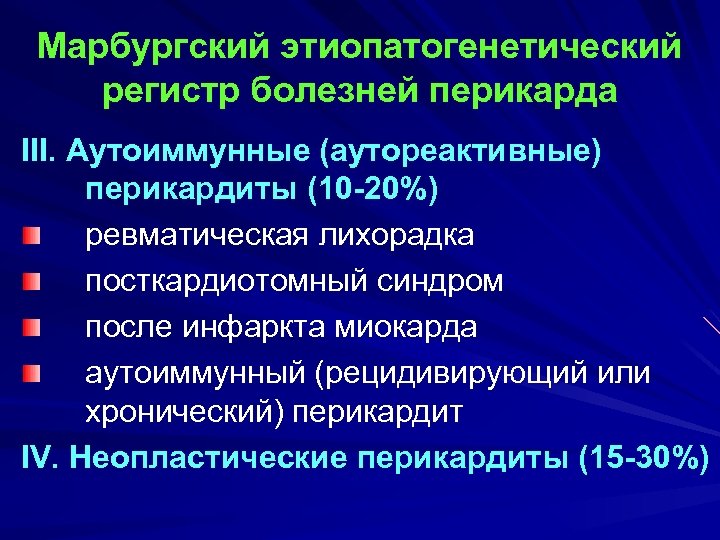

Марбургский этиопатогенетический регистр болезней перикарда III. Аутоиммунные (аутореактивные) перикардиты (10 -20%) ревматическая лихорадка посткардиотомный синдром после инфаркта миокарда аутоиммунный (рецидивирующий или хронический) перикардит IV. Неопластические перикардиты (15 -30%)